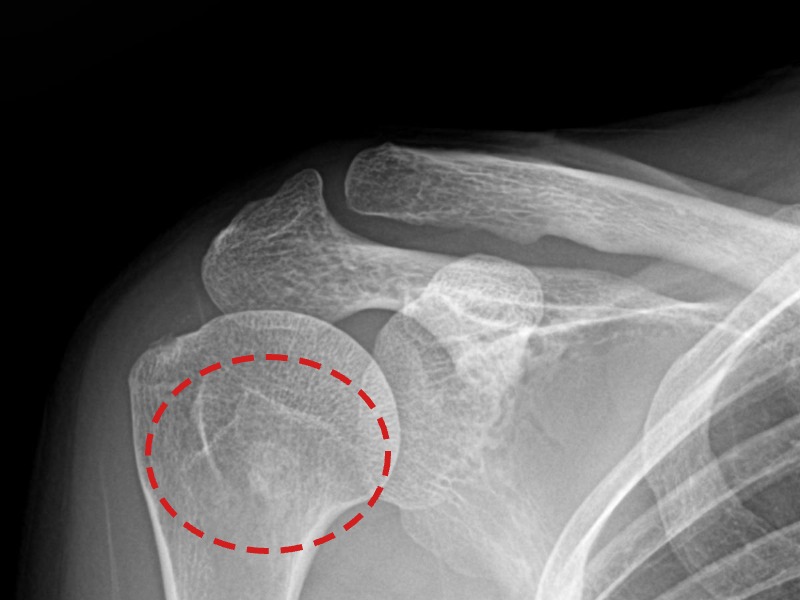

[촬영시기:21.08.30~21.09.09]

[석회분쇄흡입술] 우측 어깨 통증으로 밤잠을 못 이루고 팔을 올리기 어려워진 30대 여성 환자로, X-ray에서 우측 극상근건 내 석회 침착이 확인되어 석회분쇄흡입술을 시행하였습니다.